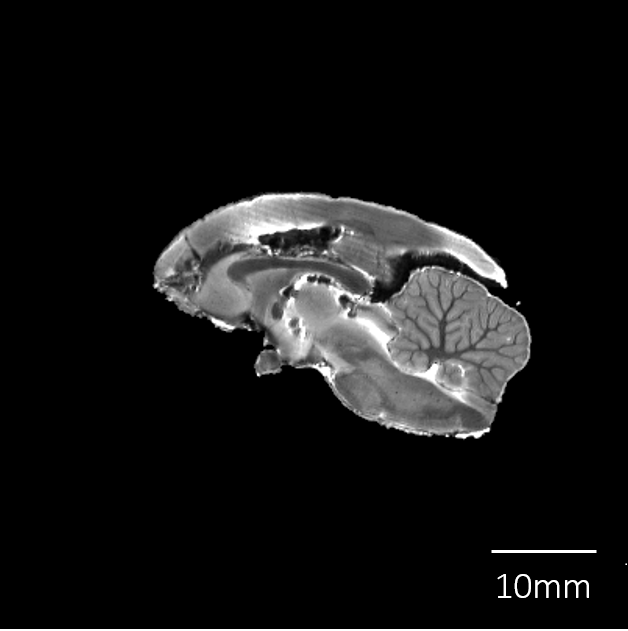

脳標本画像

| T2強調画像 |